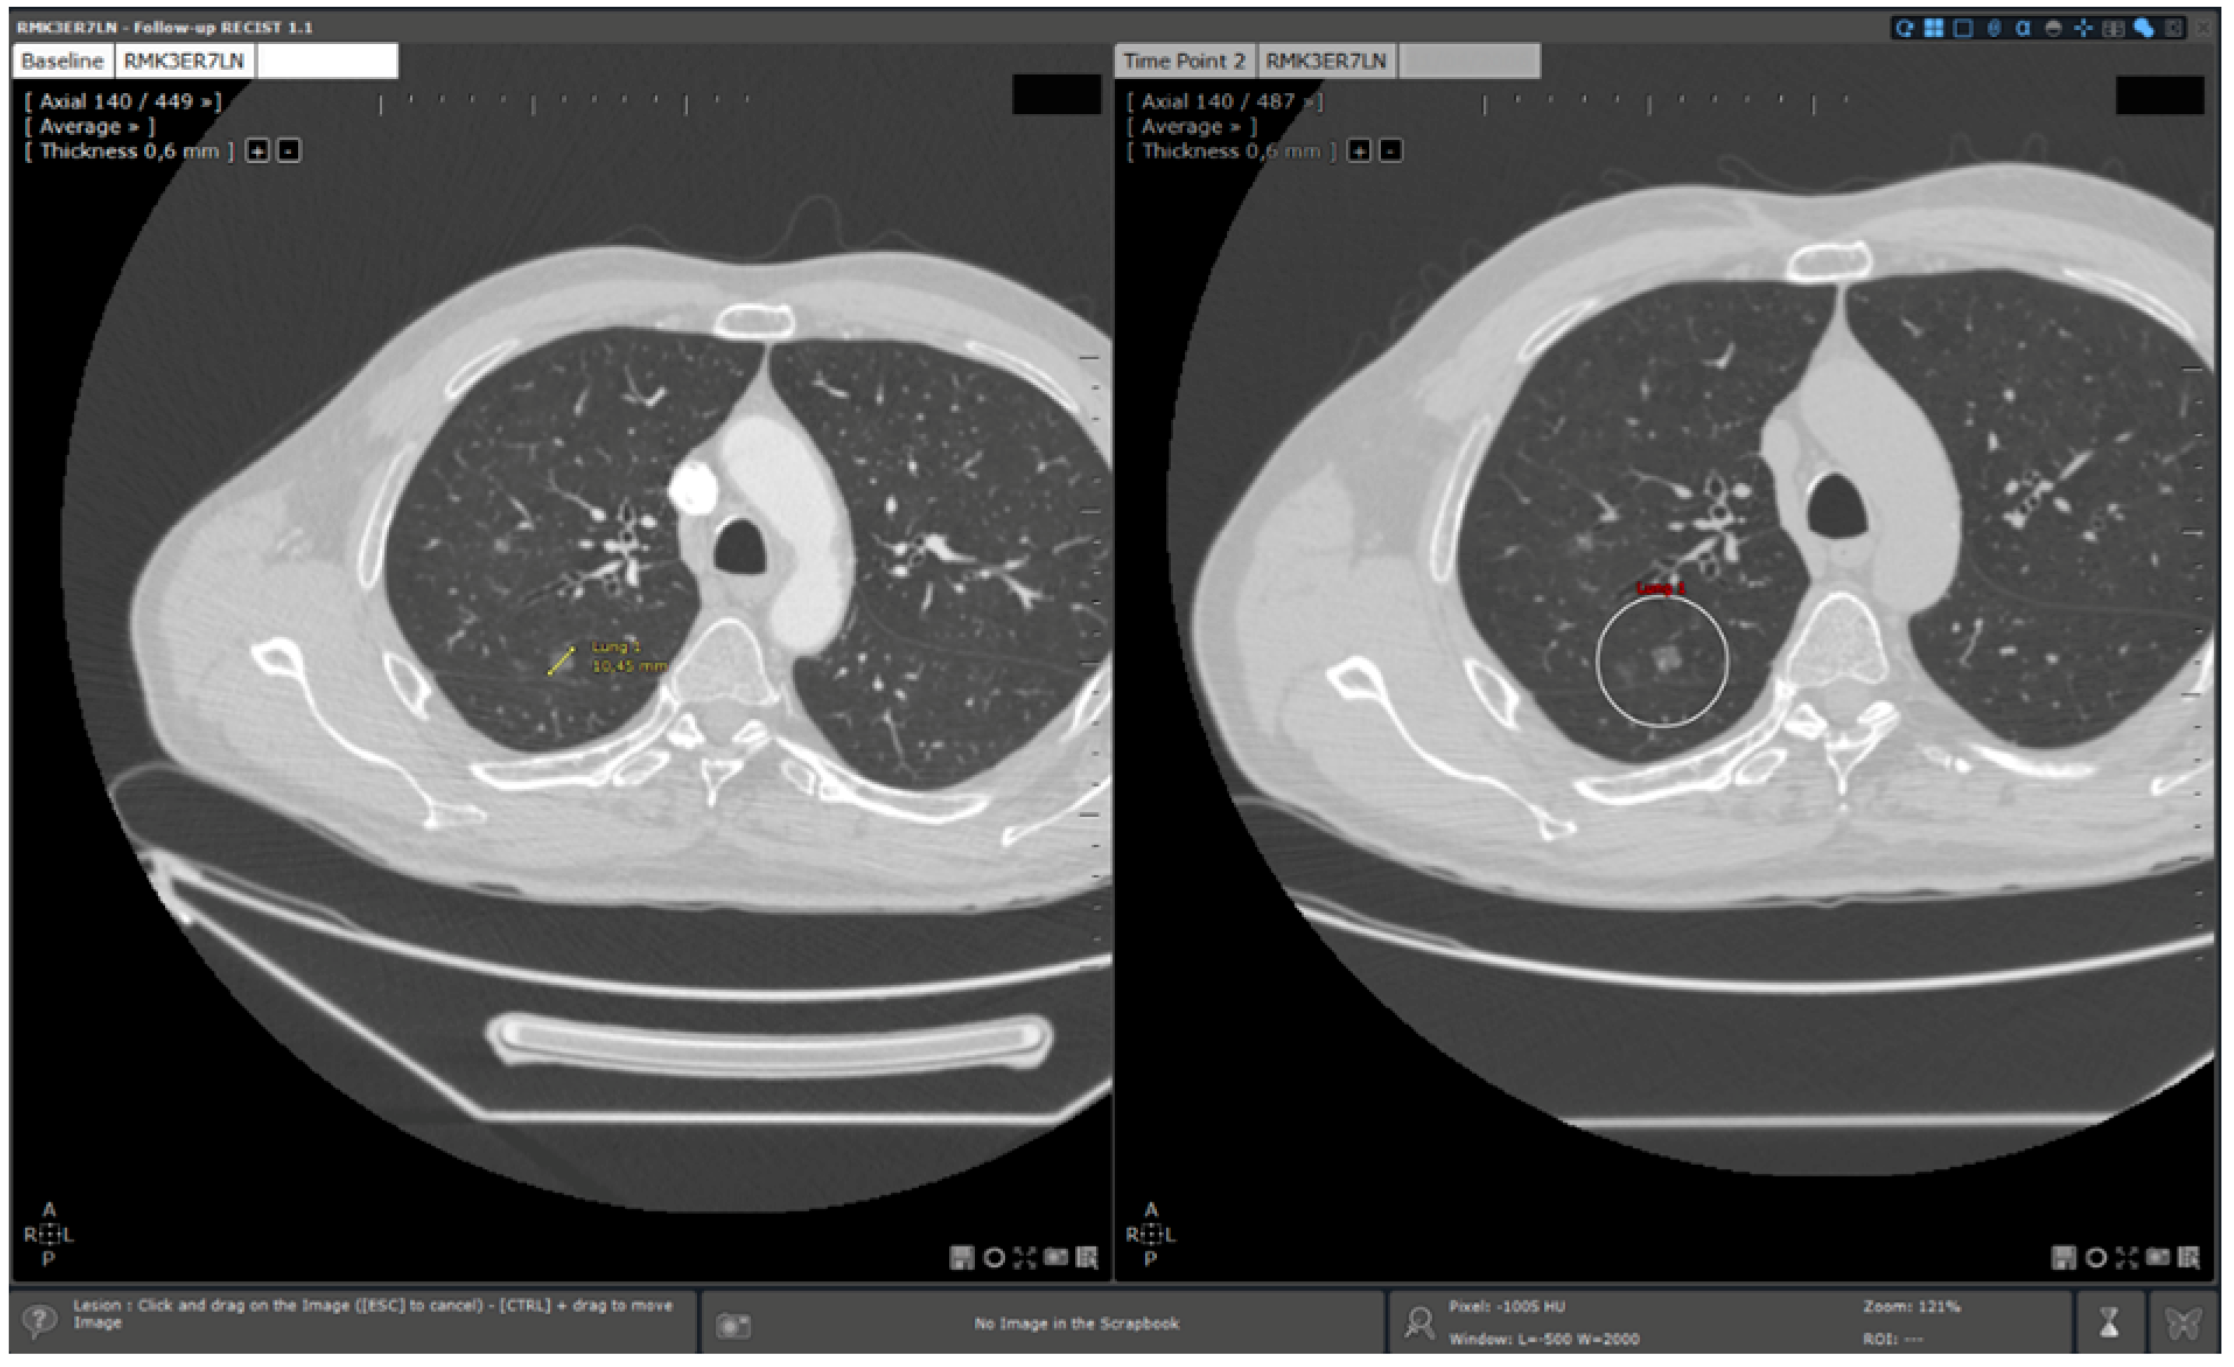

- Standard reading: Manual determination of RECIST response using a standard viewer (Myrian®, Intrasense, France) without specific options dedicated to oncologic follow ups. This reading is called “manual reading” in the rest of the article.

- Reading with dedicated software: Determination of RECIST response with the dedicated application for oncologic follow ups, Myrian® XL-Onco, with specific functionalities:

- 3D target matching technology to facilitate lesion localisation in the follow up study.

| Step 2 | Baseline study opening | Manual | Automated |

| Step 3 | Target localisation on baseline study | Manual | Automated |

| Step 4 | Target localisation on follow up study | Manual | Automated |